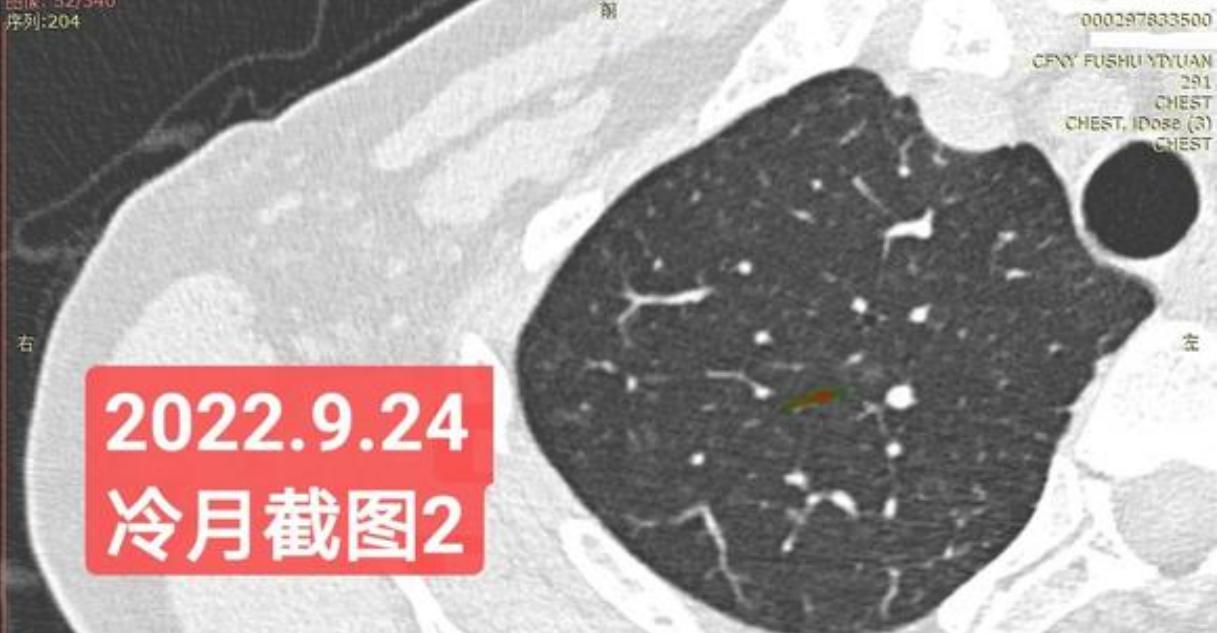

非常感谢戴主任和冷月等几位吧主的无私奉献,你们牺牲自己的休息时间,为广大患者排忧解难,你们对待病人,如同亲人一样,真的好感动!上次,在贴吧里咨询过戴主任关于我的肺结节情况,戴主任说,我右肺下叶那个结节高危。心里好害怕,距离上次CT间隔三个月,我又做了肺部CT,这次还要劳烦戴主任以及吧主们,帮我看看我的肺结节,严重吗?需要马上手术吗?

我昨天把我五次肺部CT电子版以及报告,发给了冷月吧主,昨天晚上,冷月吧主就为我截好图,发给我,非常令我感动,谢谢您冷月吧主,您辛苦了,您要多休息,不要太辛苦了。

我是21年7月做肺部CT,报告给报出0.5厘米肺结节。(但大夫说,20年就已经有那个肺结节了,因为小,报告没给报)。自发现肺结节后,吃了四个月中药,结节没有缩小,反而增大了。今年8月1日开始到现在,又吃了近两个月的蒙药了。 结节还是没有缩小,反而在增大。21年7月到现在,复查过3次肺部CT了。结节一直在增大。最近一次复查时间是2022年9月24日。

上次找戴主任贴吧咨询过,主任说我右肺下叶那个结节高危,距离上次CT,到现在三个月复查肺部CT。所以9月24日又复查做了肺部CT。

右下肺结节高危,肺窗已经到亚实性阶段CTR>0.5,纵膈窗可见实性,目前已经不属于异质混磨,而且PSN亚实性结节。